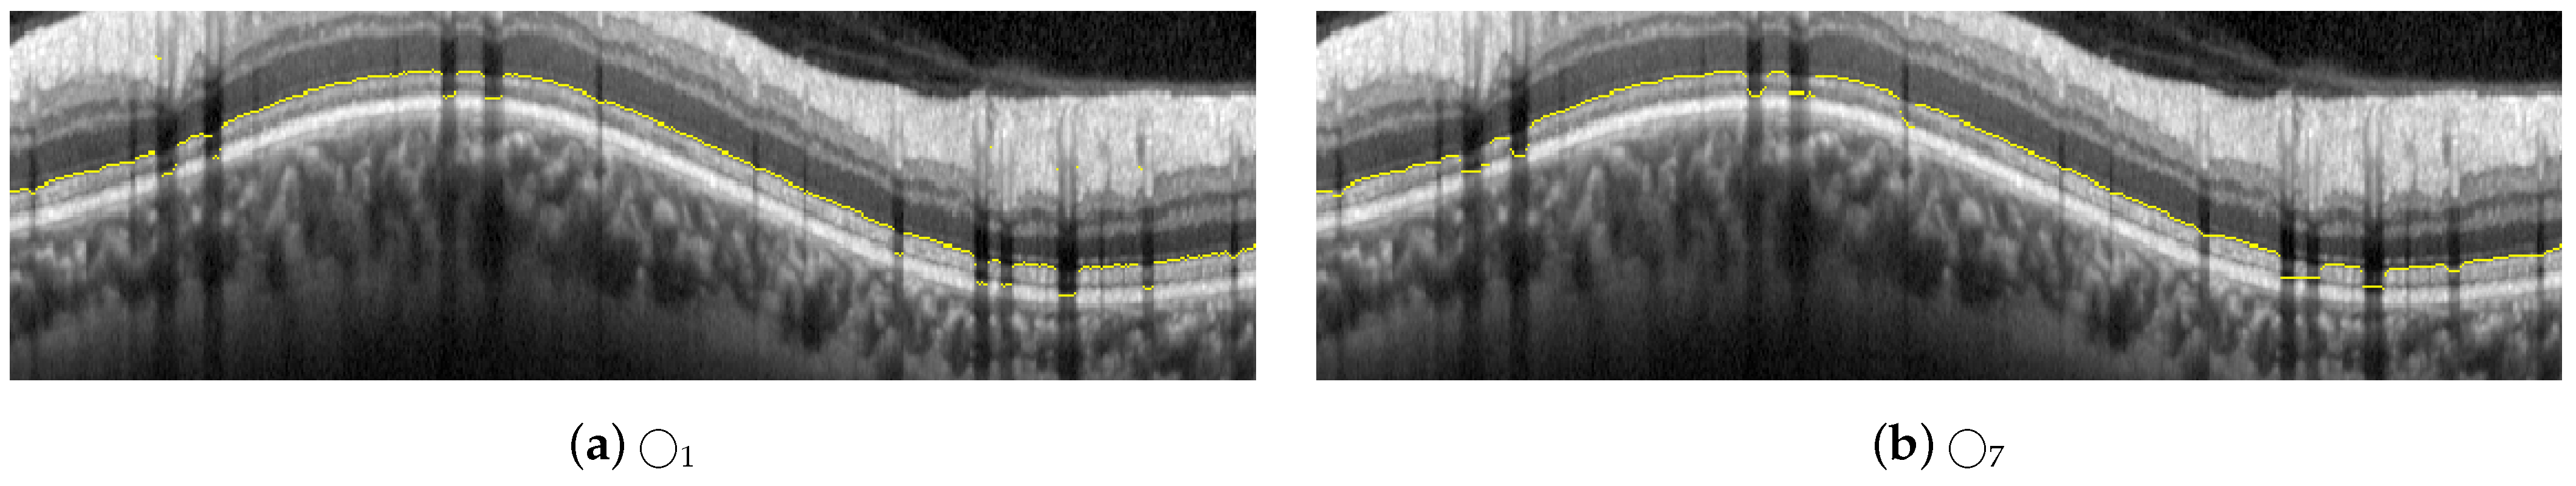

Example of a peripapillary B-scan OCT image with the manual segmentation of the layer of interest RNFL and description of the sectors: T, TS, NS, N, NI, and TI.

In order to obtain the thickness of the RNFL layer, it is first necessary to accurately segment it. The automatic segmentation of this layer can be very challenging due to the characteristics of the image in general and of the RNFL in particular. As depicted in Figure 3, OCT images often show a speckle noise, a low level of contrast, and irregularly shaped morphological features [5,6].

As can be seen in Figure 3 and Figure 4, the RNFL is the innermost layer of the retina. Granular noise and various artifacts appear in the area of the image above the RNFL, which corresponds to the vitreous body. These artifacts have similar grayscale levels to the layer of interest, which leads to a more challenging segmentation process. Moreover, the transition between the RNFL and the CGL, which is located just below the RNFL, shows a low level of contrast, making the separation between these two layers a relevant issue [22].

Figure 4.

Layers of the retina from top to bottom. RNFL: retinal nerve fiber layer; GCL: ganglion cell layer; IPL: inner plexiform layer; INL: inner nuclear layer; OPL: outer plexiform layer; and ONL: outer nuclear layer. Boundary delineation in the segmentation process. #1-UB: upper boundary of the RNFL; #2-AB: auxiliary boundary corresponding to the lower boundary of the ONL; #3-LB, lower boundary of the RNFL. The dashed boxes exemplify some of the artifacts of the layers.